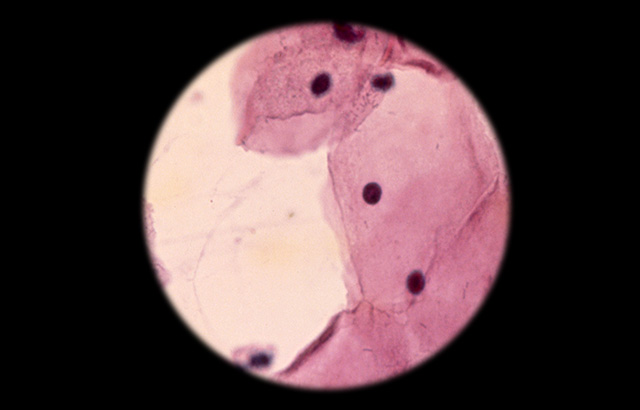

A cytologic smear under the microscope